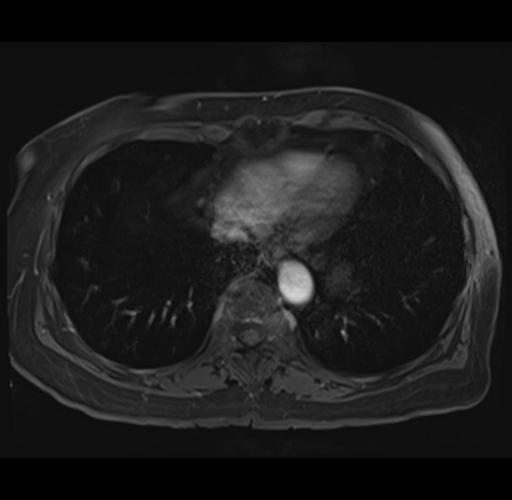

MRI T1